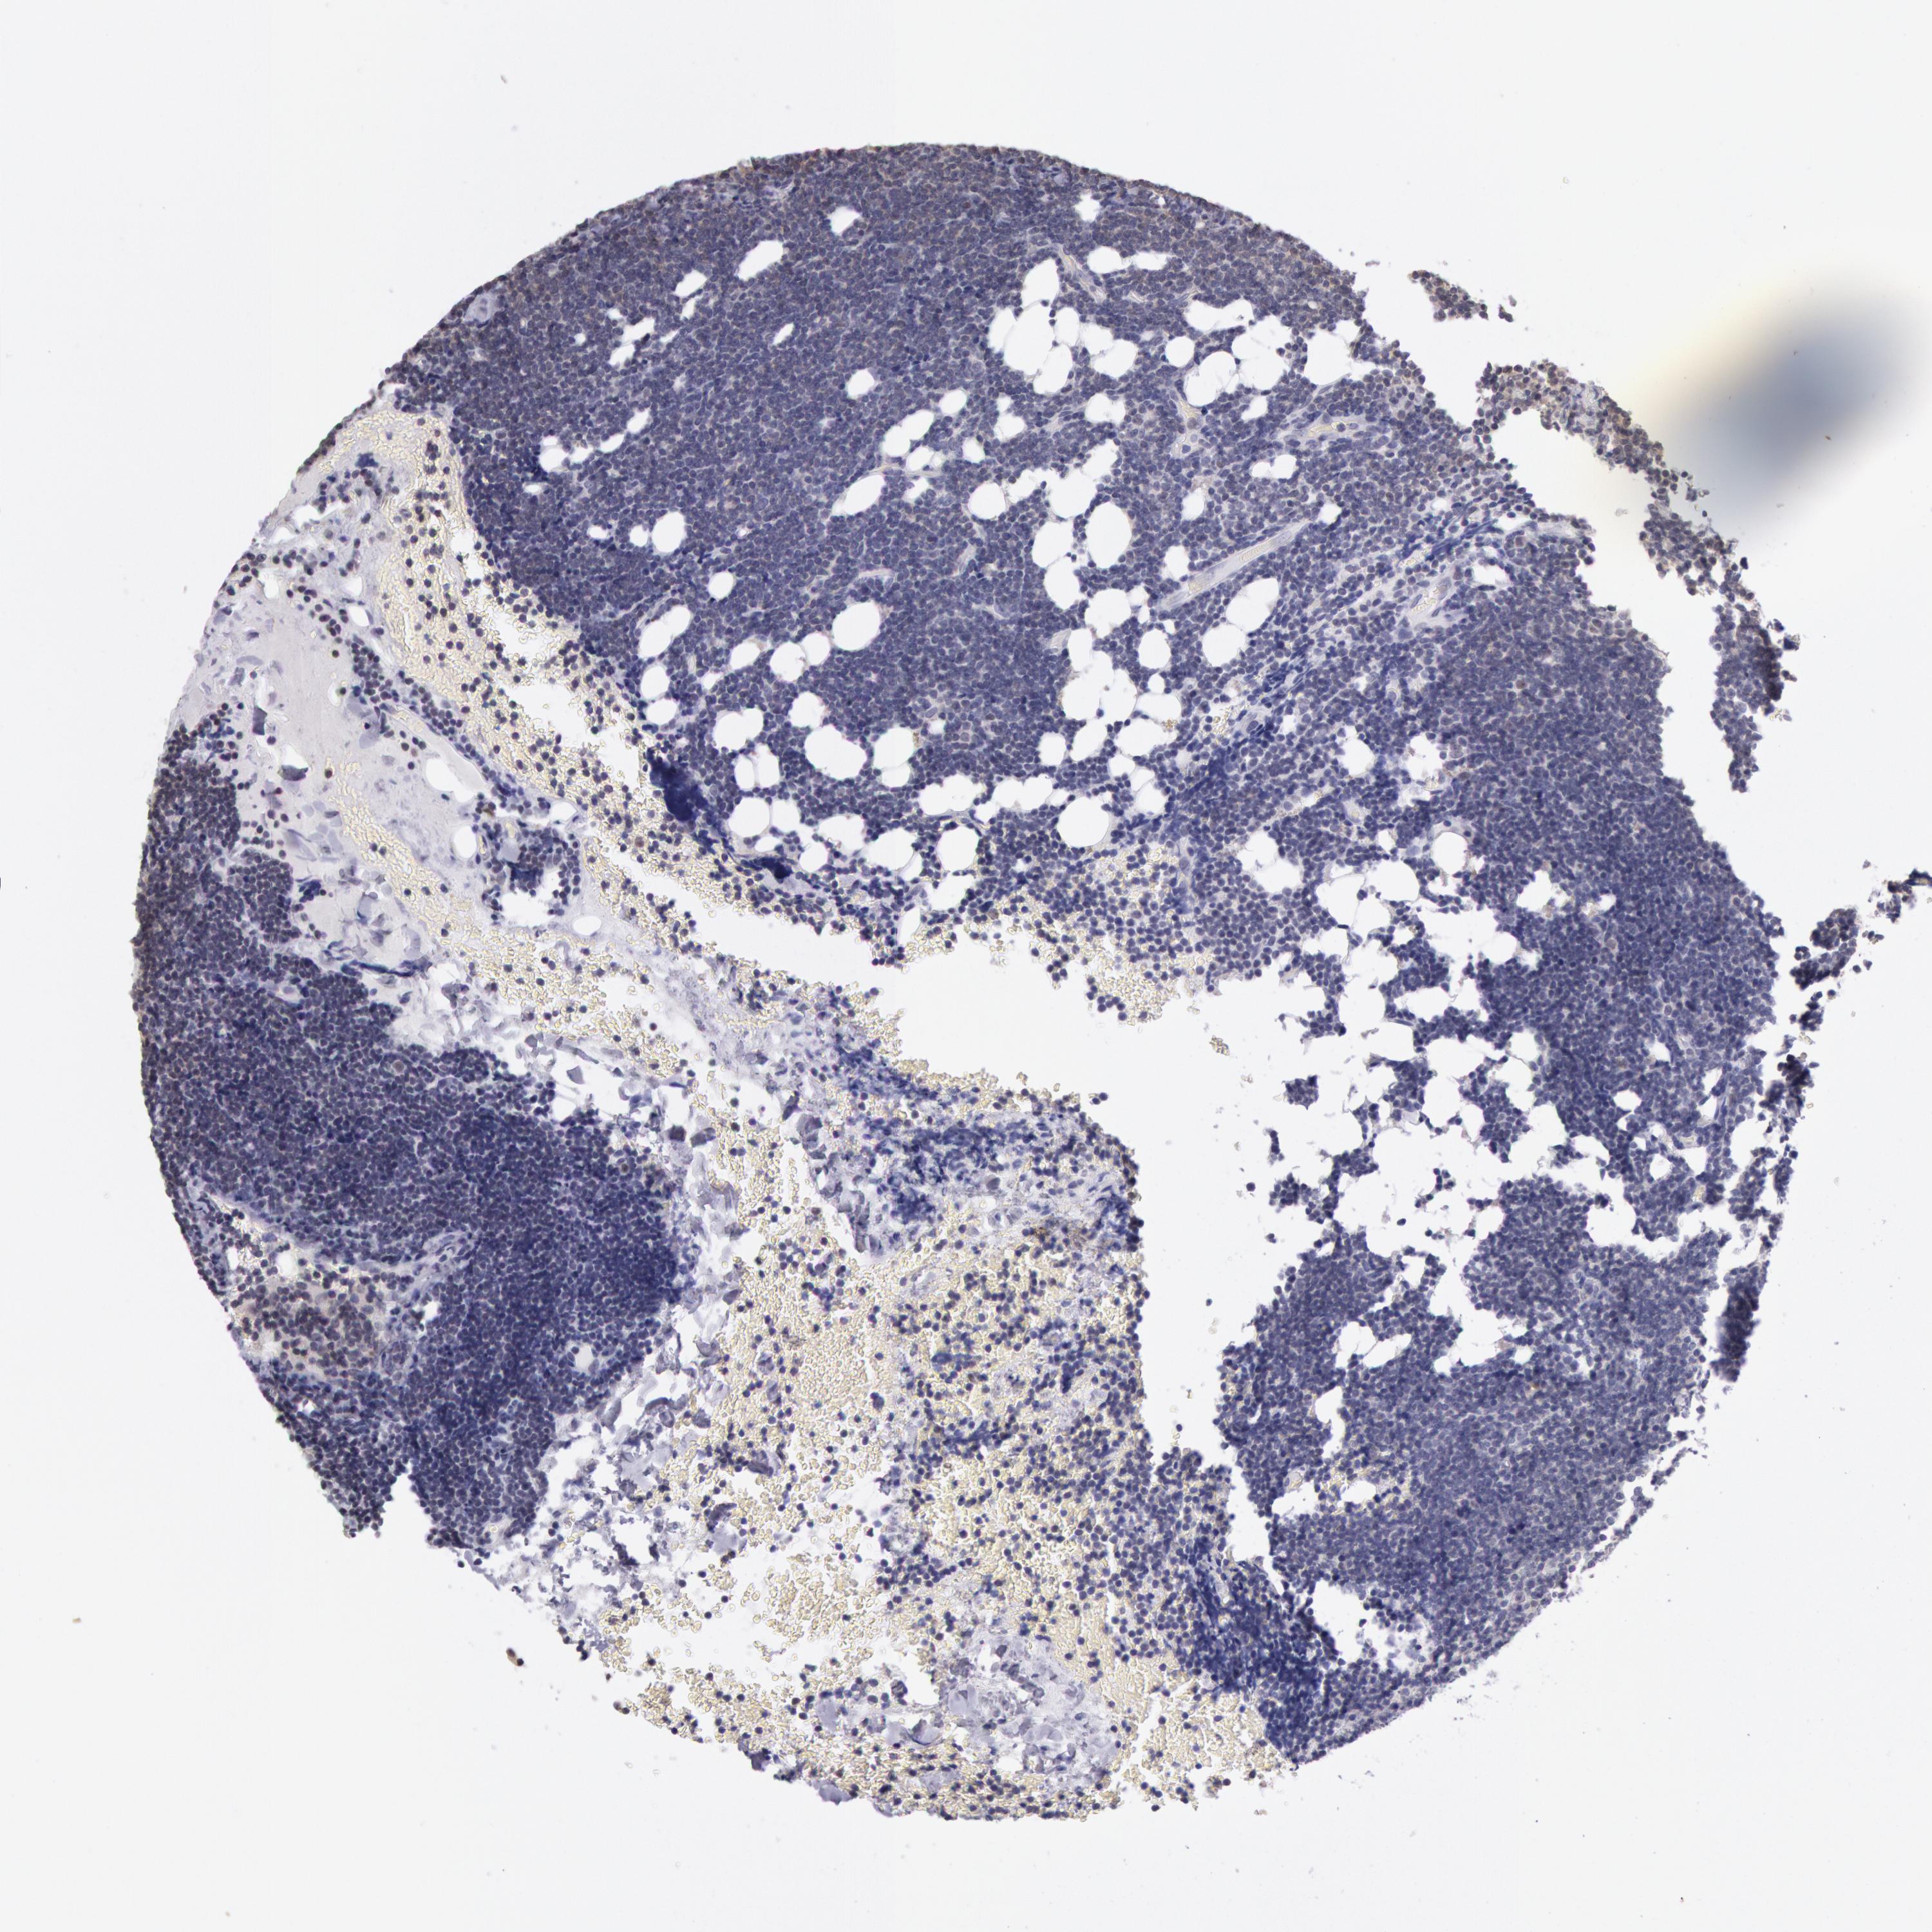

CANCER LYMPHOMA Show tissue menu

LYMPHOMA - Protein expressioni

A mouse-over function shows sample information and annotation data. Click on an image to view it in a full screen mode. Samples can be filtered based on level of antibody staining by selecting one or several of the following categories: high, medium, low and not detected. The assay and annotation is described here.

Each image is clickable and will lead to virtual microscopy that enables deeper exploration of all samples and also displays staining intensity scores, fraction scores and subcellular localization as well as patient and tissue information for each sample.

Antibody HPA001275

Antibody CAB017442

Malignant lymphoma, non-Hodgkin's type, High grade

Hodgkin's disease, NOS

Malignant lymphoma, non-Hodgkin's type, Low grade